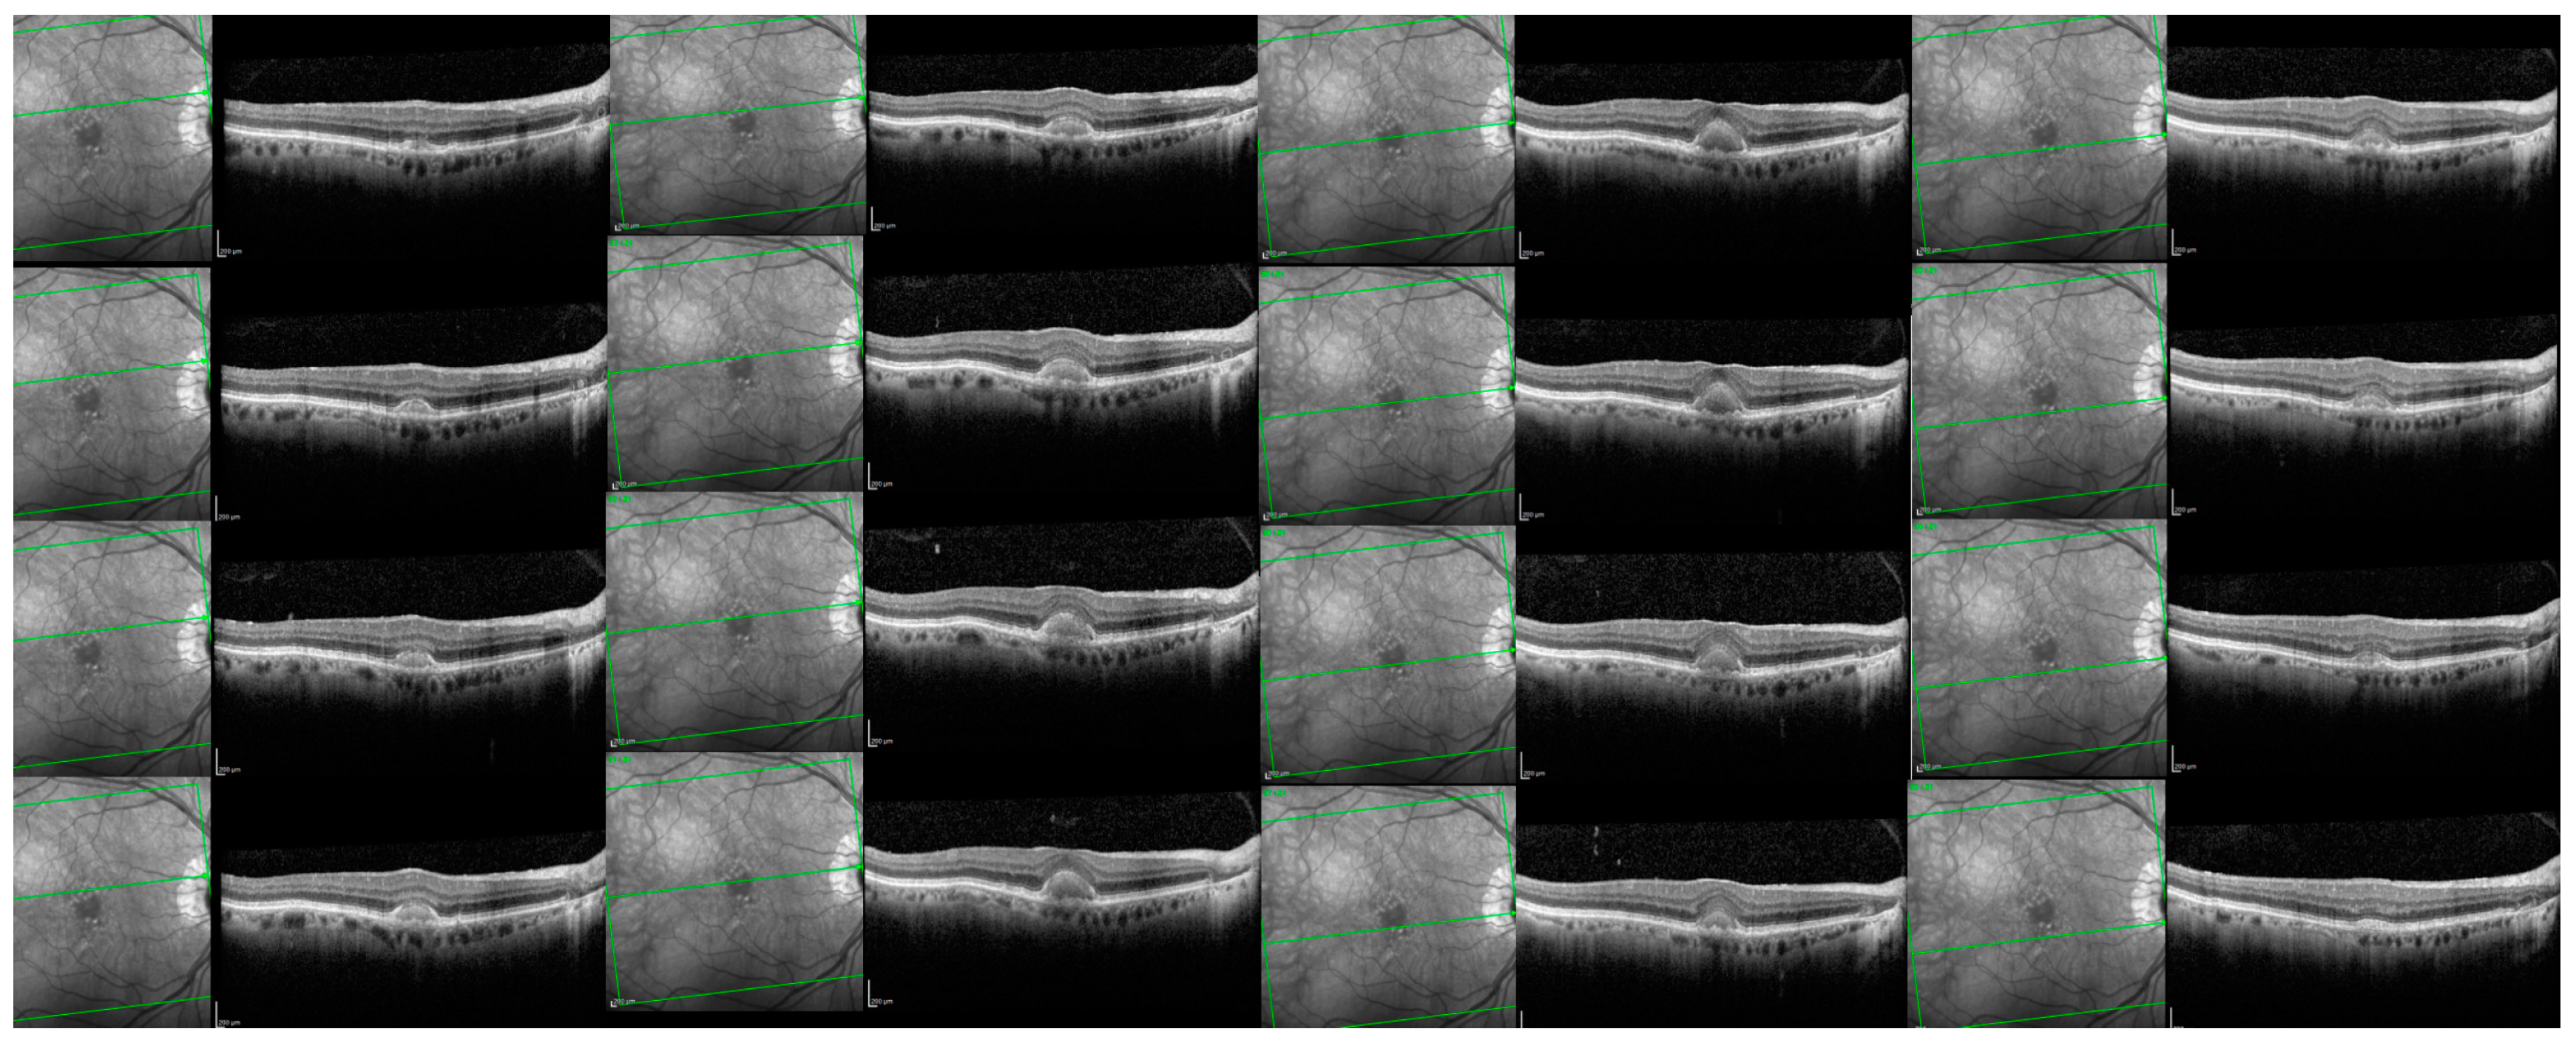

At baseline, 16/18 (88.9%) eyes presented a vitelliform stage while 2/18 (11.1%) presented a vitelliruptive stage. In terms of the OCT features found in our study eyes containing AVLs, 9 eyes (50%) had associated SDD, 8 eyes (44.4.%) had cuticular drusen, 4 eyes (22.2%) had soft drusen, 9 eyes (50%) had HRF, 5 eyes (27.8%) had SRF, 2 eyes (11.1%) had PED, and 3 eyes (16.6%) had no other findings, except the vitelliform lesion. The qualitative analysis showed a continuous ELM in 10/18 eyes (55.5%), a discontinuous ELM in 6/18 eyes (33.3%) and an indistinguishable ELM in 2/18 eyes (11.1%). EZ was continuous in 4/18 eyes (22.2%), discontinuous in 13/18 eyes (72.2%) and indistinguishable in 1/18 eyes (5.5%) (see Table 1 and Figure 4).

We further illustrated 2 representative cases. An 85-year-old patient, with a vitelliform lesion in the RE, with a BCVA of 80 ETDRS letters at baseline (see Figure 5A). After 25 months and 4 anti-VEGF Bevacizumab injections, the lesion increased in size (see Figure 5B). In the next 14 months, he received another 2 anti-VEGF injections with Bevacizumab and 2 anti-VEGF injections with Aflibercept (see Figure 5C). The lesion transformed into vitelliruptive while the BCVA was 70 ETDRS letters (see Figure 5E).

Figure 6 presents the case of a 71-year-old patient with a small vitelliform lesion in his LE, with a BCVA ETDRS of 75 letters (A). Forty-three months later, the lesion increased, with a BCVA ETDRS of 75 letters (B).

Figure 4. Associated retinal lesions. SD-OCT B-scans passing through the AVLs of clinical study eyes; (A) the green circles show SDD and the white arrow continuous ELM; (B) the brown circles show cuticular drusen; (C) the red arrow shows a drusenoid PED and the yellow star the vitelliform deposit; (D) the yellow star shows the vitelliform deposit, the purple arrow an HRF, the blue arrow head the RPE thickening; (E) the yellow star shows the vitelliform deposit, the purple square the SRF; (F) the white arrow indicates a continuous ELM and the black arrow a continuous EZ; (G): the black arrow indicates a discontinuous EZ and the blue arrow head the RPE thickening; (H) the white arrow indicates a indistinguishable ELM and the black arrow an indistinguishable EZ.

Biomedicines 11 01382 g004

Figure 5. Spectral-domain OCT (SD-OCT) in a patient with AVL presenting the vitelliform stage at baseline (A); after 4 anti-VEGF injections with Bevacizumab, respectively 25 months later, the lesion increased (B); after another 2 anti-VEGF injections with Bevacizumab and 2 injections with Aflibercept (C), respectively, after another 14 months; after another 2 months the lesion started to shrink (D); after another month the lesion resorbed (E).

Biomedicines 11 01382 g005

Figure 6. Spectral-domain OCT (SD-OCT) in patient with AVL presenting the vitelliform stage at baseline (upper image) and 43 months later at last visit (lower image).

Biomedicines 11 01382 g006